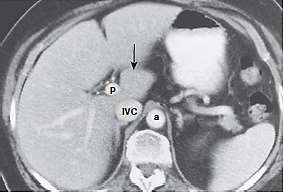

O exame de tomografia computadorizada de abdome com contraste é muito utilizado para a identificação de estruturas e delimitação de lesões, sendo, muitas vezes, essencial no diagnóstico de determinadas patologias. Segundo a segmentação hepática proposta por Couinaud (1957), assinale a alternativa que apresenta o segmento hepático que está sendo apontado pela seta preta na figura a seguir.

Tomografia computadorizada com contraste do fígado. Veia